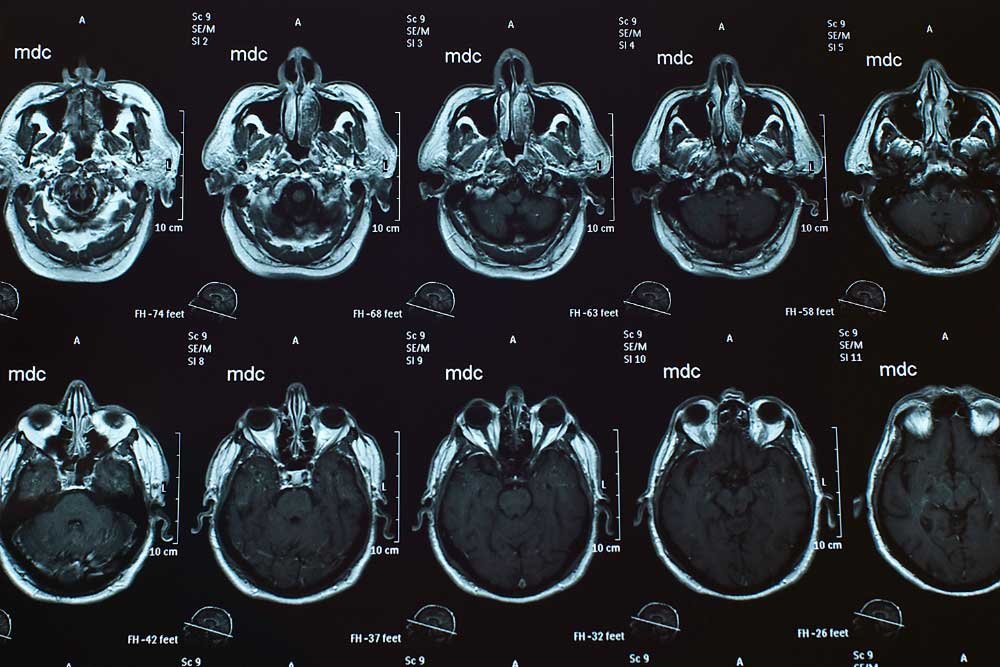

CT scans are a useful tool for taking X-ray images of the body to help diagnose tumors, locate internal bleeding, or assess other internal injuries or damage. CT scans can also be used to take tissue or fluid samples for biopsy.